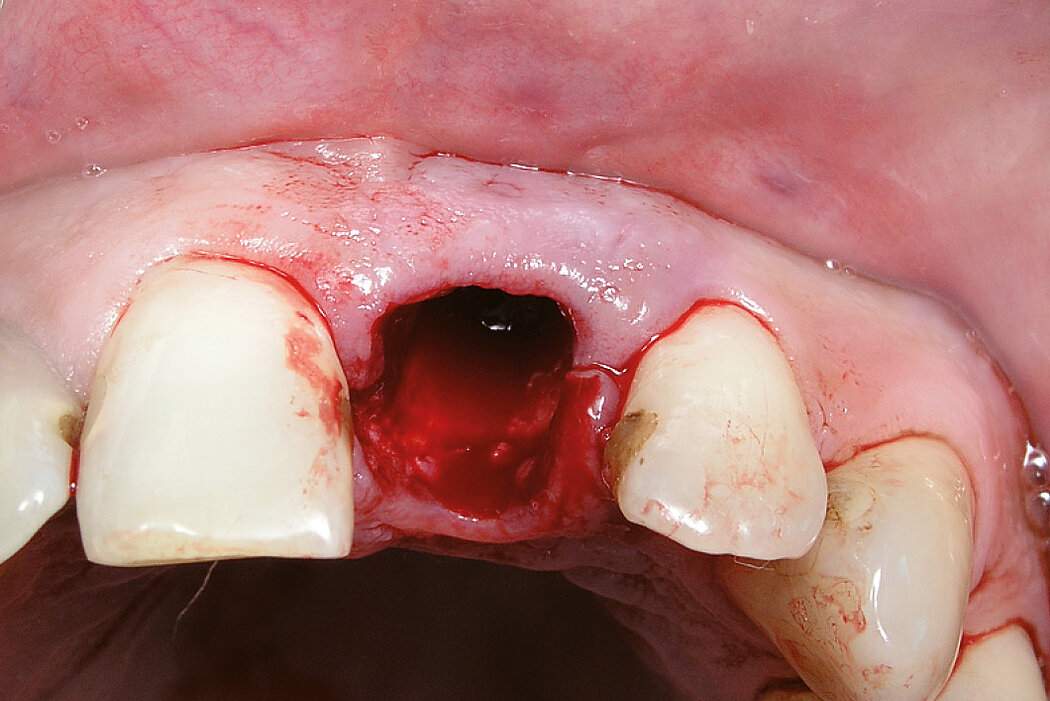

颊侧骨壁完整时的牙槽窝内牙槽嵴保存

病例来自 Dr. Stefan Fickl

德国,维尔茨堡

临床挑战

软硬组织保存完好,颊侧或咬合面无任何瘢痕。

目的/方法

拔牙后4个月延期种植。牙槽窝的微创治疗。

结论

治疗后4个月,骨状况良好/成熟/牢固。快速且无瘢痕的软组织再生。患者获得最佳的临床效果和美学效果。